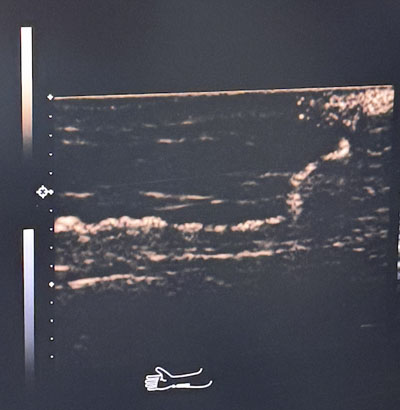

术前超声造影